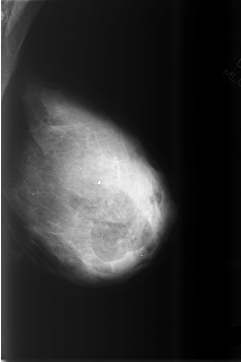

C_0505_1.LEFT_MLO

C_0505_1.LEFT_CC

LEFT_MLO LINES 5784 PIXELS_PER_LINE 3856 BITS_PER_PIXEL 12 RESOLUTION 50 NON_OVERLAY